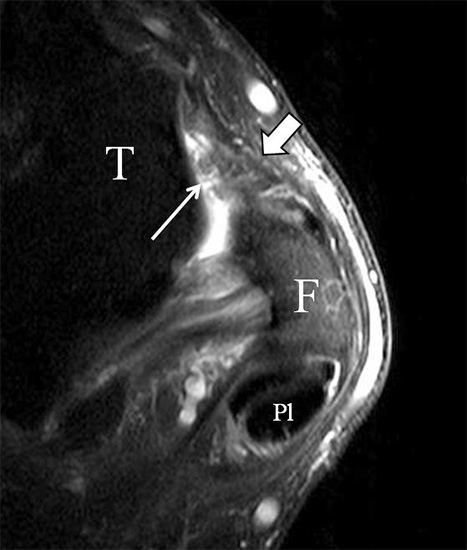

Der Ursprung des Ligamentum fibulocalcaneare liegt unmittelbar kaudal und dorsal des Ursprungs des Ligamentum fibulotalare anterius, so dass gehäuft kombinierte Verletzungen und auch ein gemeinsamer knöcherner Ausriss beobachtet werden. Nach kaudal dorsal verläuft das Band dann nach medial konvex unter die Peroneussehnen. Danach ist ein schräg deszendierender, gestreckter Verlauf bis zum calcanearen Ansatz abgrenzbar (Abb. 10). Dieser zu allen drei Standardebenen schräge Verlauf erschwert häufig die Diagnostik des LFC vor allem bei subtileren Verletzungen. Spezialprojektionen, die dem Bandverlauf orthograd folgen (entweder schräg coronar oder schräg sagittal) erleichtern auch hier die Diagnostik (Abb. 11) insbesondere nicht dislozierter Avulsionen. Assoziierte Verletzungen der Peroneussehnenloge müssen mit beurteilt werden, wobei neben Verletzungen der Sehnen und Sehnenscheiden die Beurteilung des Retinaculum peroneum superius und inferius wichtig ist. In einem Kollektiv von Patienten mit chronischen Außenbandinstabilitäten weisen 50% der Patienten eine Verletzung dieser Strukturen auf 5. Auch hier erleichtern hochauflösende Techniken die Diagnostik (Abb. 12).